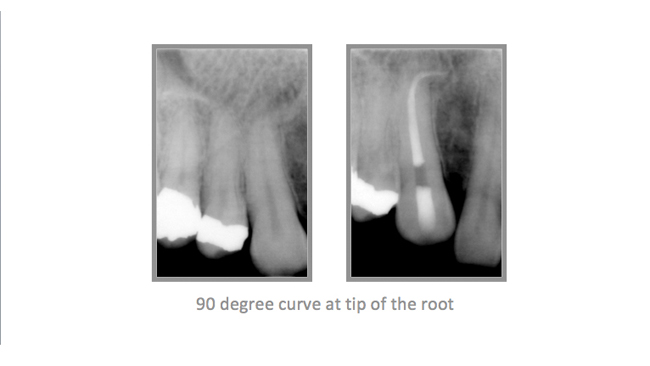

• A few Teeth Treated by Dr. Katsarsky